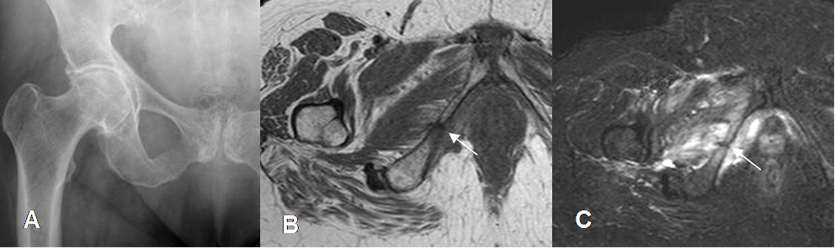

Fig 70 B. Fractura de stress.

A: Rx AP, donde no se detectan anormalidades.

B: RM coronal en STIR: Edema del cuello femoral, con fractura lineal a nivel transcervical.

C: Rx AP. Control luego de 1 mes, donde se aprecia imagen lineal y densa, que corresponde al callo óseo.